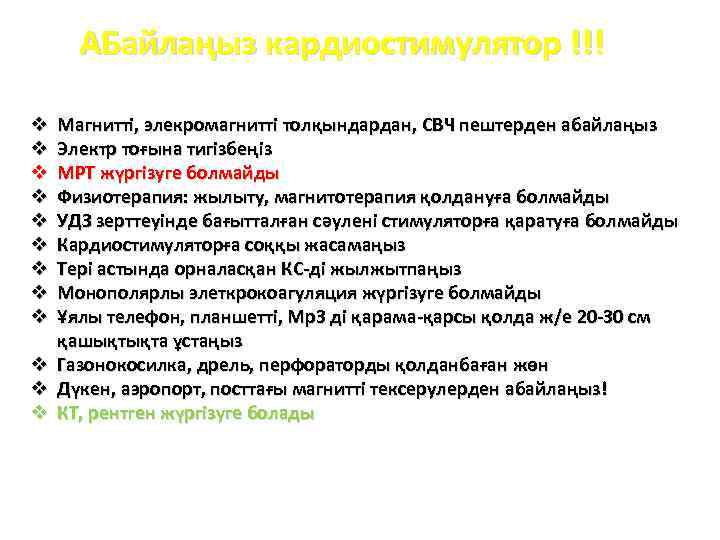

АБайлаңыз кардиостимулятор !!! Магнитті, элекромагнитті толқындардан, СВЧ пештерден абайлаңыз Электр тоғына тигізбеңіз МРТ жүргізуге болмайды Физиотерапия: жылыту, магнитотерапия қолдануға болмайды УДЗ зерттеуінде бағытталған сәулені стимуляторға қаратуға болмайды Кардиостимуляторға соққы жасамаңыз Тері астында орналасқан КС-ді жылжытпаңыз Монополярлы элеткрокоагуляция жүргізуге болмайды Ұялы телефон, планшетті, Мр3 ді қарама-қарсы қолда ж/е 20 -30 см қашықтықта ұстаңыз v Газонокосилка, дрель, перфораторды қолданбаған жөн v Дүкен, аэропорт, посттағы магнитті тексерулерден абайлаңыз! v КТ, рентген жүргізуге болады v v v v v

АБайлаңыз кардиостимулятор !!! Магнитті, элекромагнитті толқындардан, СВЧ пештерден абайлаңыз Электр тоғына тигізбеңіз МРТ жүргізуге болмайды Физиотерапия: жылыту, магнитотерапия қолдануға болмайды УДЗ зерттеуінде бағытталған сәулені стимуляторға қаратуға болмайды Кардиостимуляторға соққы жасамаңыз Тері астында орналасқан КС-ді жылжытпаңыз Монополярлы элеткрокоагуляция жүргізуге болмайды Ұялы телефон, планшетті, Мр3 ді қарама-қарсы қолда ж/е 20 -30 см қашықтықта ұстаңыз v Газонокосилка, дрель, перфораторды қолданбаған жөн v Дүкен, аэропорт, посттағы магнитті тексерулерден абайлаңыз! v КТ, рентген жүргізуге болады v v v v v